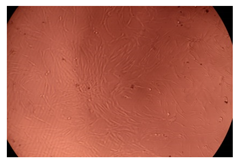

2.4. In Vitro Cytotoxicity Analysis

| Control |  |  | |

| Cop B | 10 µg/mL |  |  |

| 50 µg/mL |  |  | |

| 100 µg/mL |  |  | |

| Cop B/IMC = 10/1 (wt/wt) | 10 µg/mL |  |  |

| 50 µg/mL |  |  | |

| 100 µg/mL |  |  | |

| Cop B/Dorzolamide = 10/1 (wt/wt) | 10 µg/mL |  |  |

| 50 µg/mL |  |  | |

| 100 µg/mL |  |  | |